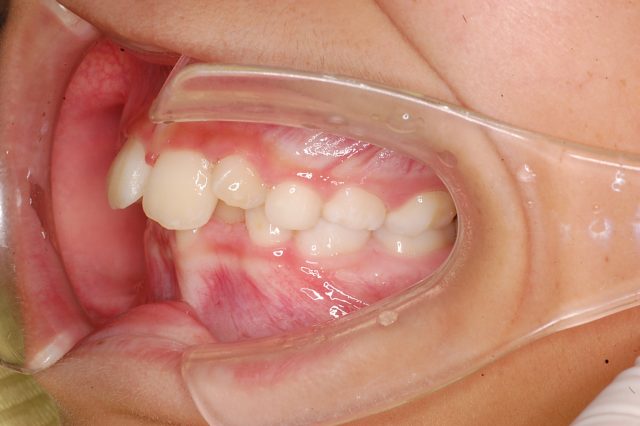

8歳男の子インビザラインファースト:永久歯スペース不足を解消

| 年齢・性別・主訴 | 8歳男の子 永久歯が並ぶスペースが足りない |

他のBefore